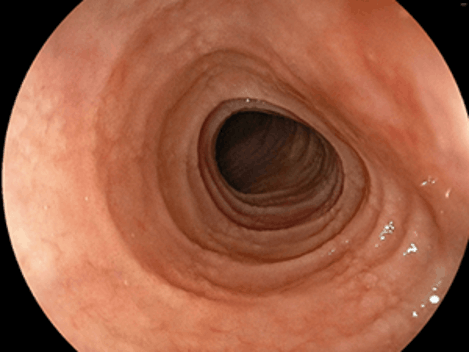

診断する上では、胃カメラ(胃内視鏡検査)が欠かせないものとなります。典型的な内視鏡像としては、食道で縦方向に長い数条の溝(縦走溝)、それと直交する何重にも渡る輪状溝(これによって食道が気管様に観察されることも)、縦走溝周囲にとくに目立つ細かい白斑となります。一方で、初期や軽症例では内視鏡的にはほとんど異常を認めないことも多いです。

縦走溝・輪状溝の見られる好酸球性食道炎

所見が強く気管様に観察されるEoEが…